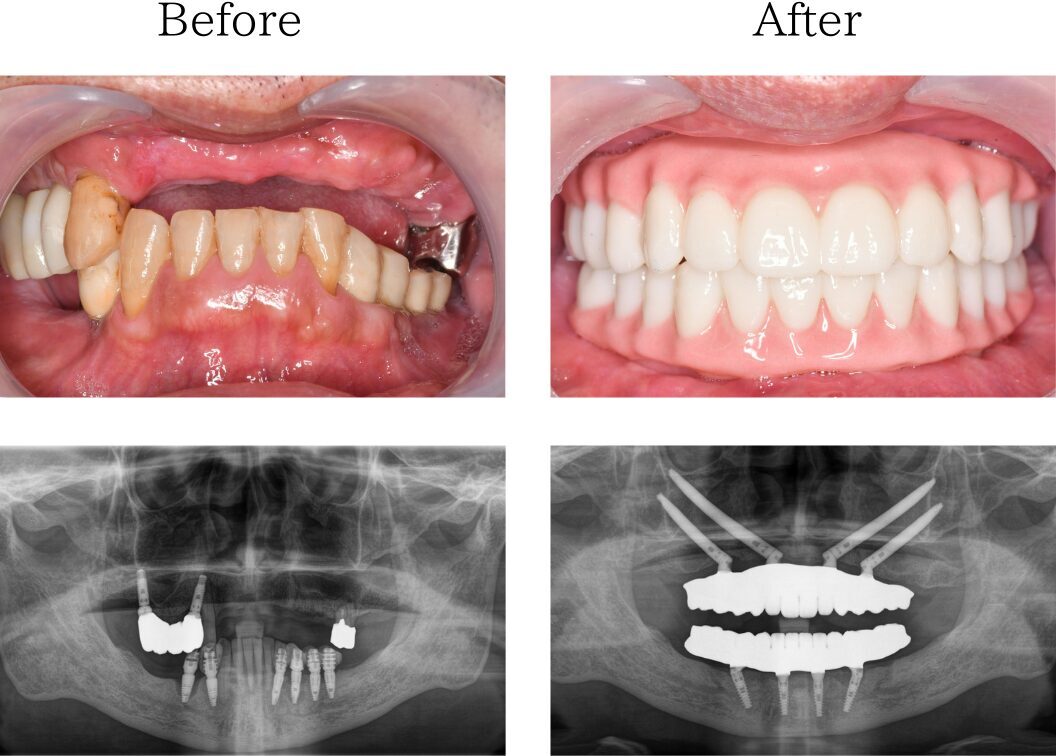

3kiritori

※治療内容:上下顎オールオン4ザイゴマ4本

※費用:4,795,000円*モニター価格

※期間:半年

※リスク:出血、痛み、腫れ、しびれ

「他院のインプラント治療に不信感」

70代 男性 (福岡) の場合

他院で入れたインプラントは一年くらいで悪くなり抜きました。その後他のインプラントも揺れ始め、その歯科医院に不信感を抱くようになり、最善の治療はないかとネットで調べていたところ、おおたわ歯科医院を見つけました。YouTubeやブログを読んでいて、大多和先生になら任せられると思い相談し、オールオン4の手術を決めました。